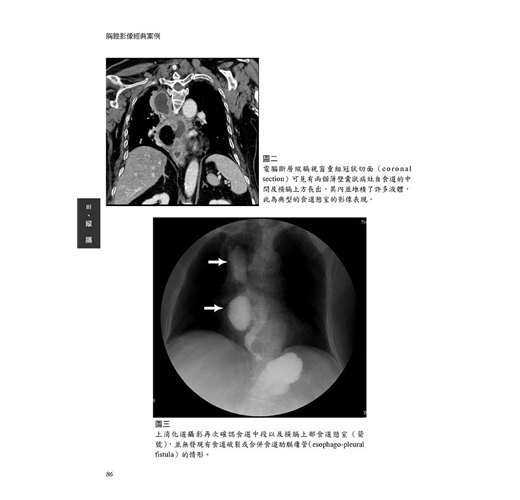

病例20 食道憩室(Esophageal diverticula) 85